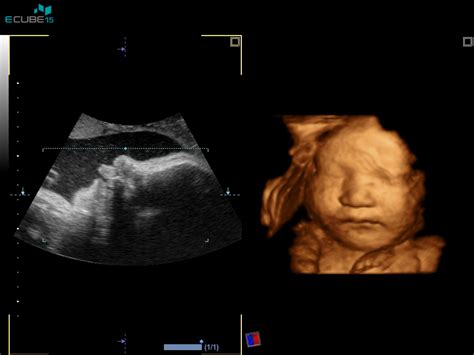

V 6. tednu nosečnosti je vaš otrok v prvih razvojnih fazah. S pomočjo ultrazvoka ga lahko vidimo kot majhno gmoto znotraj amnijske ovojnice. V tem obdobju se oblikujejo najpomembnejše osnovne strukture, vključno s posteljico in popkovino, ki bosta zagotavljali preskrbo s hranili. Otrokovo srce že bije zelo hitro. Telo se intenzivno pripravlja na prihod novega življenja, kar se odraža tudi v številnih fizičnih spremembah pri materi. Hormonske spremembe so izrazite in lahko povzročajo različne simptome, ki se običajno pojavljajo v prvem trimesečju. Med te sodijo jutranja slabost, občutljivost dojk, utrujenost, nihanje razpoloženja in spremembe v cirkulaciji.